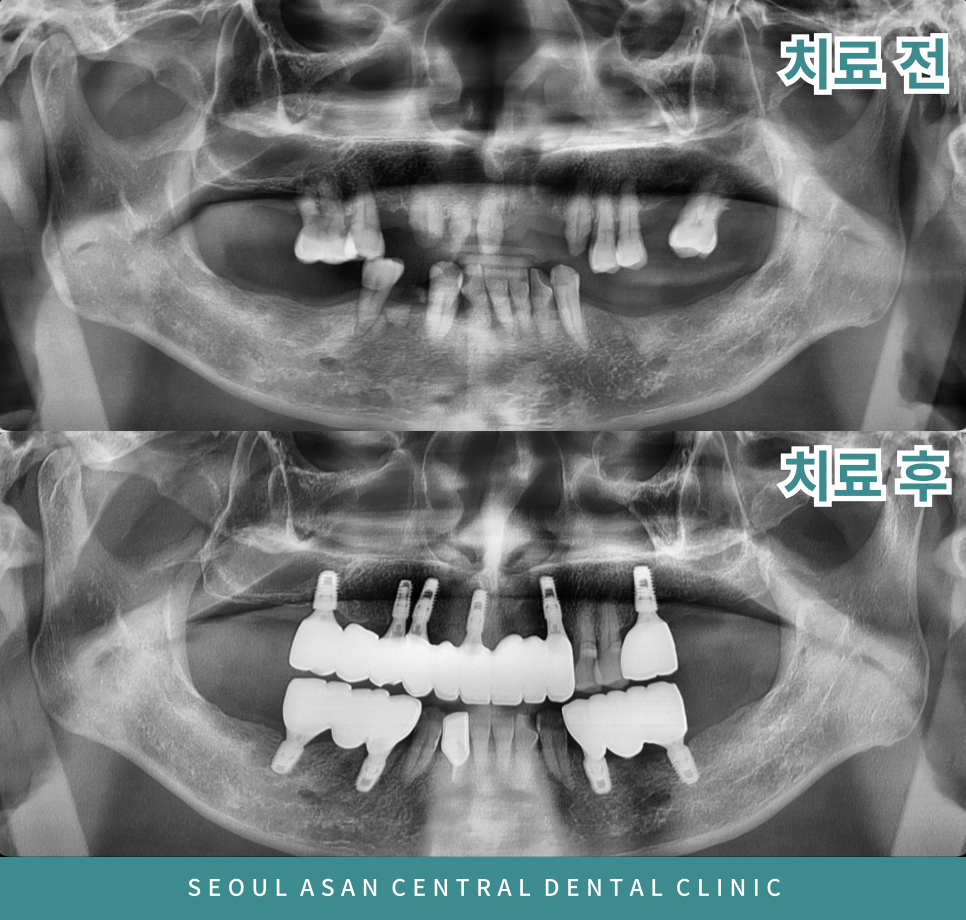

다수의 치아 상실과 위턱 앞니의보철물이

빠진 상태로 지내 오시다가 불편감이 있다면

발치 후 임플란트와 신경치료를 동반하여

크라운 수복을 진행되는게 좋습니다.

더불어 충치가 많이 남아있거나,

뿌리만 남아있는 경우,

발치 후 신경치료 후 크라운 수복을 통해

치아를 보존하게 됩니다.

제일 먼저 전반적인 치주 상태가 좋지 않다면

전체적인 스케일링 후 예후가 좋지 않은 곳을 발치를 진행한 뒤

임시틀니를 제작하여 치료가 마무리되기 전까지

일상생활에서의 불편감을 줄일 수 있도록 도와드려야 합니다.

발치 부위가 어느 정도 회복하였을때는

은행동임플란트 식립을 진행하게 되는데요.

상실된 부위와 발치를 진행하는 부위의

기존 개수에 맞게 진행해 준다면 제일 좋겠지만

잔존 잇몸뼈의 상태와 경제적인 여건 등을 고려하여

임플란트 브릿지로 진행할 수 있습니다.

임플란트 브릿지란 다수의 치아를 상실하였을 때

필요한 인공치근을 식립하고 크라운을

브릿지 형태로 제작해서 씌우는 방법으로

임플란트와 브릿지 치료가 결합된 형태의 방법입니다.